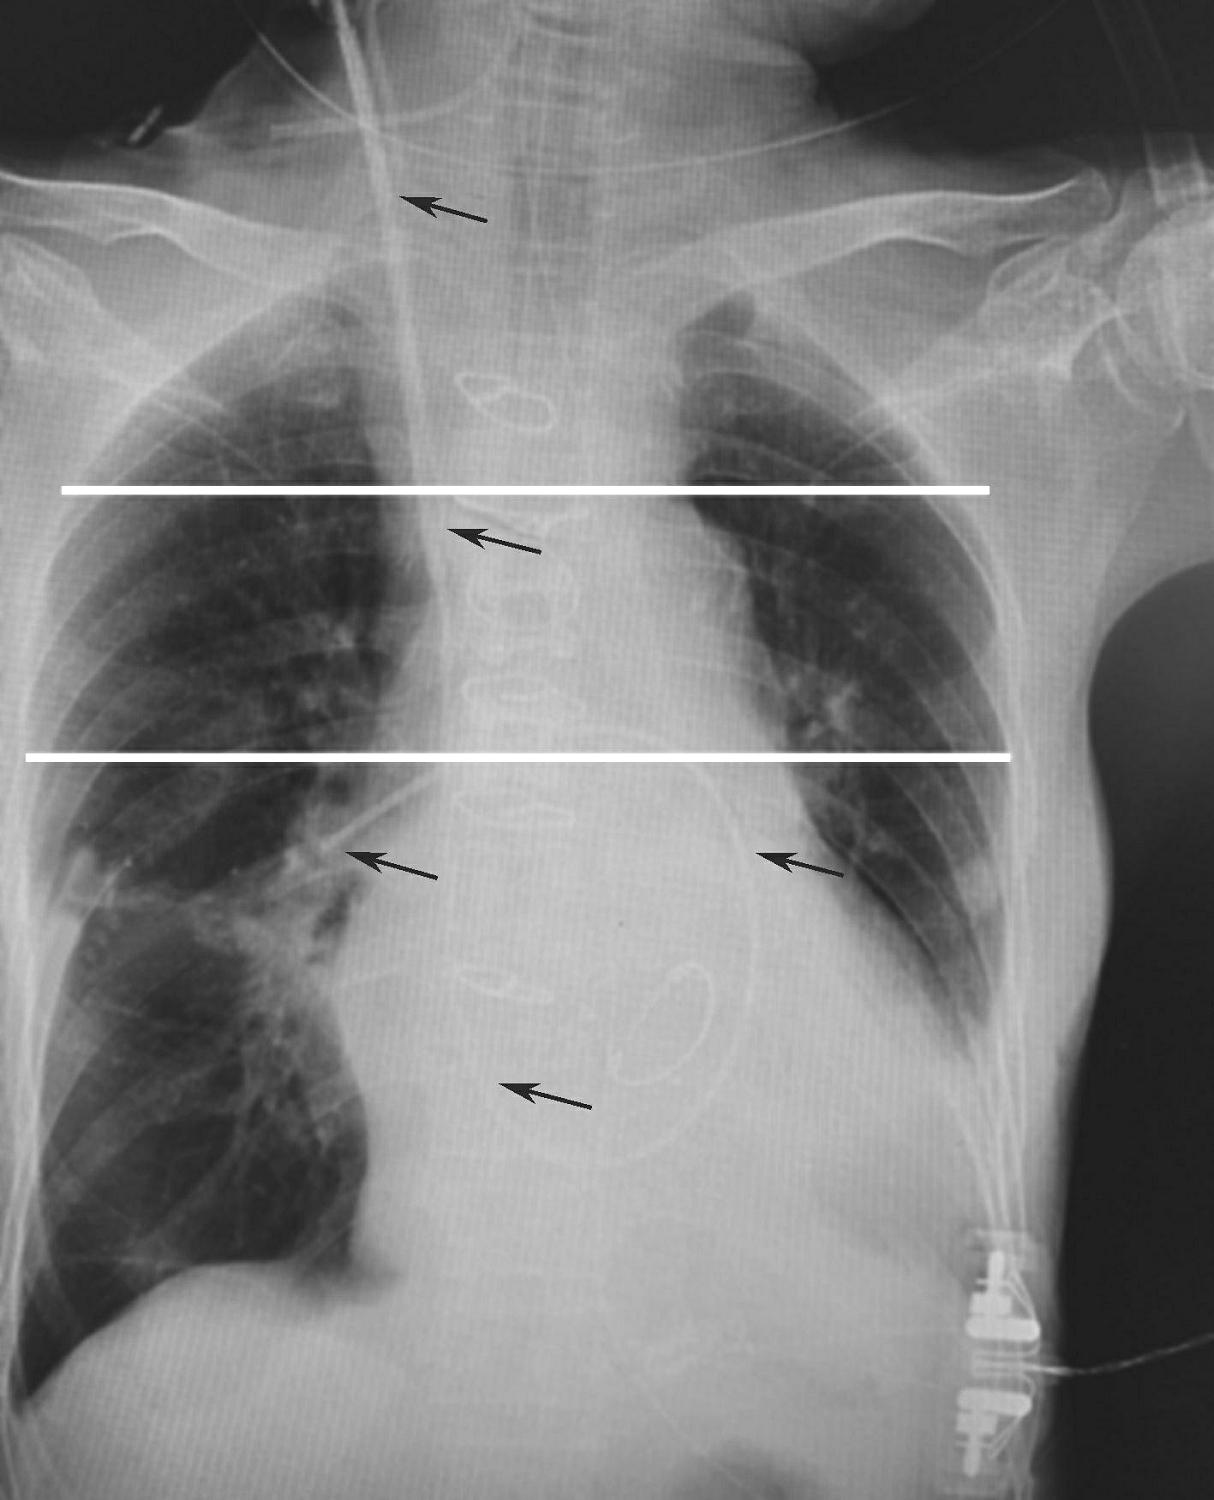

6.导管置入完成后,常规行床旁胸片检查,明确导管位置。漂浮导管的最佳位置是肺的west分区Ⅲ区,此处的压力由高到低为肺动脉压(P a )、肺静脉压(P v )、肺泡压(P A ),因此左心房压估测的准确度相对较高(图3-1-6)。

图3-1-6 漂浮导管置入至正确位置的胸片表现

黑色箭头示肺动脉导管。